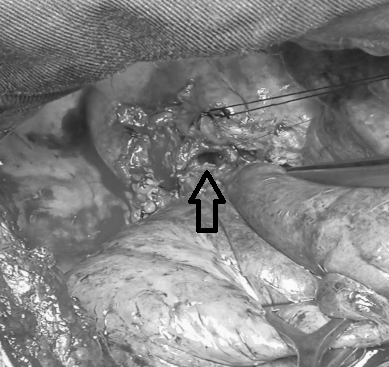

由于手术难度大,术中不可预知情况多,经过术前讨论高兴才主任认为,患者右主支气管狭窄长度约1-2cm,可实施“支气管成形术”,虽然有术中切除肺叶的可能,但患者比较年轻,应尽最大可能保留右肺上叶。经过积极术前心肺功能准备后,于7月16日,高兴才主任医师、冯光强副主任医师在麻醉科胡强夫主任及其团队的配合下,全麻双腔插管给霍先生实施了“右主支气管成形术”。打开胸腔后发现,胸腔广泛粘连,而且因为炎症的原因,患者组织脆、水肿,解剖发育异常,都给手术增加了难度。但是,为了保留患者右上肺,术者仔细操作,认真分离,终于完整切除了狭窄的气管,同时成功吻合断端,术中患者顺利脱机后返回病房。

▲ 箭头所示修剪后的远端支气管(气管内乳白色物为积存痰液和脓液)

▲ 箭头所示正在重建支气管